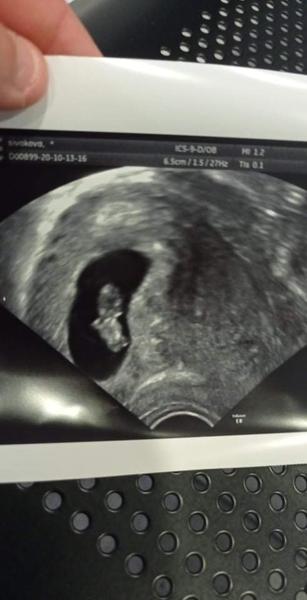

Bříško. Co myslíte?

Ahoj chtěla sem se zeptat jsem 7tt těhotná ale nemám žádné bříško jen mám jen ale příznaky časté čůrání hlad občas motání hlavy měli jsme už přišlo nebo ještě ne aby nepotratila protože dneska ne zabolelo nějak bříšku a občas ne tam píchá na jedné straně